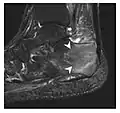

a

a b

b

Figure 10: Calcaneal fatigue fracture in a 30-year-old male runner. Radiographs were normal (not shown). (a) Sagittal T1-weighted and (b) short tau inversion recovery images show a linear hypointensity (arrows) of calcaneal tuberosity within diffuse bone marrow edema, which appears as an ill-defined area of hyperintensity on a fluid sensitive pulse sequence (arrowheads).[1]